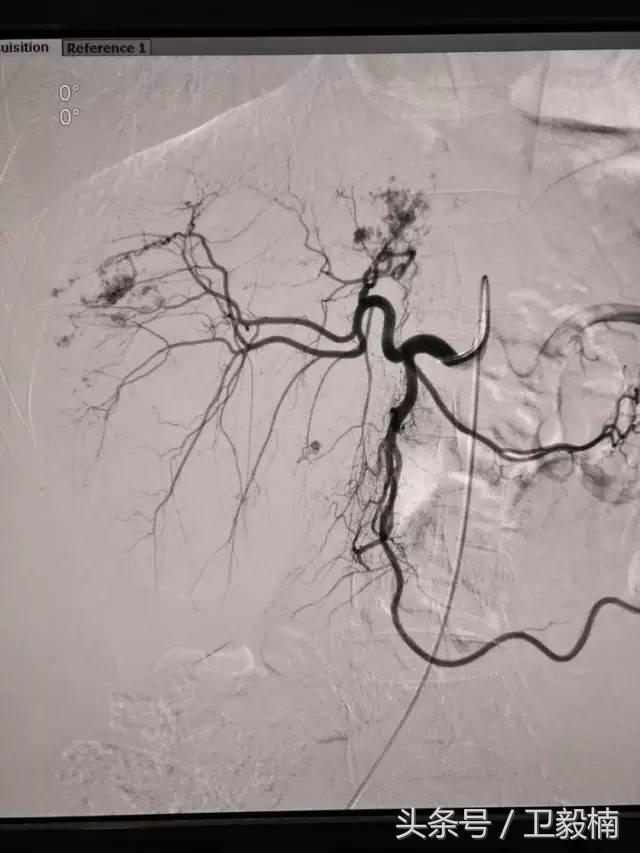

一、全身各部位血管造影;

亦称介入性血管造影学(Interventional angiography),是指在诊断性血管造影的同时,自导管向血管管腔内注射药物或某些物质或施行某种措施,以达治疗目的。常用血管介入技术有三种。

2、经导管血管栓塞法(Transcatheter embolization)

经原血管造影的导管或特制的导管,将栓塞物送至靶血管内,一是治疗内出血如外伤性脏器出血、溃疡病、肿瘤或原因未明的脏器出血。另一是用栓塞法治疗肿瘤,因肿瘤循环部分或全部被栓塞物阻断,以达控制肿瘤之生长,或作为手术切除的一种治疗手段;亦可用于非手术脏器切除,例如注射栓塞物质于脾动脉分支内,即部分性脾栓塞,以治疗脾功亢进,同时不影响脾脏的免疫功能。